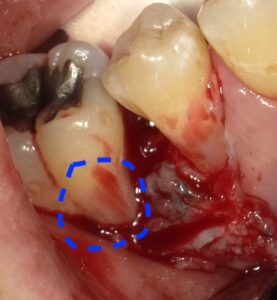

画像の様なイメージになります。針金を使いませんので

見た目がよくまた維持力も大きくとても良好な義歯となります。